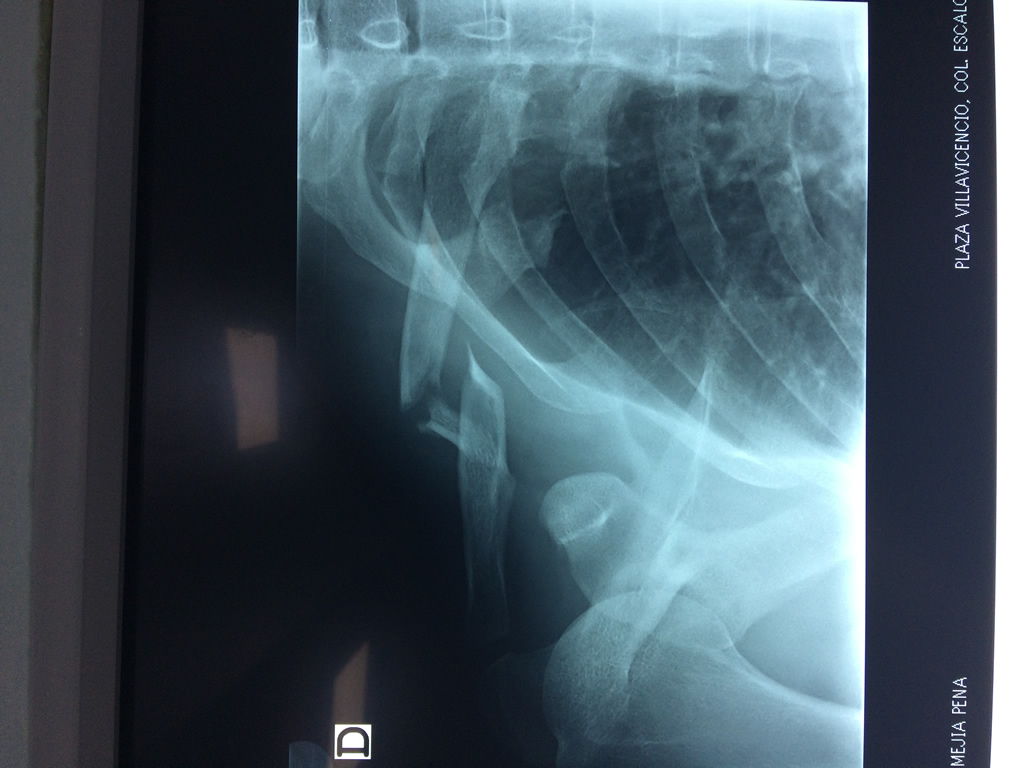

Cirugías de Húmero - Clavícula

La clavícula es un hueso largo, con forma de "S" itálica, situado en la parte anterosuperior del tórax. Junto con la escápula forman la cintura escapular. Se puede palpar por toda su longitud y se extiende del esternón al acromion de la escápula, siguiendo una dirección oblicua lateral y posterior.

Se considera el único medio de unión entre el miembro superior y el tórax. A pesar de su aspecto, similar al de un hueso largo, posee una estructura semejante a la de un hueso plano, ya que carece de epífisis y de diáfisis, lo que la harían entrar dentro de la clasificación de hueso largo. Carece de un canal medular propiamente dicho.